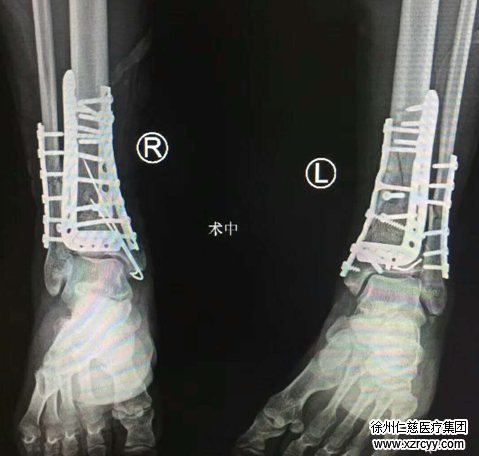

术中,手术团队聚精会神,分工协作,先进行右踝关节骨折的复位及内固定。在右外踝侧做10厘米长切口,见关节粉碎严重,予以手法复位腓骨远端骨折端,六孔钢板固定;小腿远折端粉碎严重,关节面消失,复位骨折块,克氏针固定,手法复位关节面,克氏针固定,L型锁定钢板固定;右踝后内侧切6厘米长切口,手法复位粉碎骨折端,克氏针固定,钢板固定。同样的方法,在左踝关节的前侧、内侧分别手法复位骨折端,克氏针固定,L型钢板固定。

手术进行了漫长的5小时35分钟,两侧小腿远端共作了4切口打了7块钢板。参与手术的袁医生说:“手术时间特别长,对体力要求很高,赵博士和我院团队合作的这台手术做得非常好。pilon骨折碎成这样的非常少见,手术难度比较大,这种双pilon骨折后期是有致残风险的,手术做得好的话风险则会大大降低。”